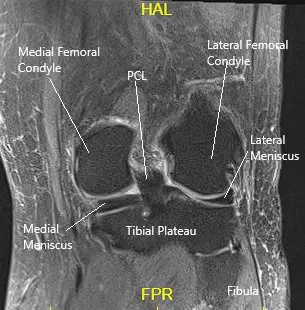

MRI of the knee in the coronal section showing various structures.

The knee joint is formed by the femur (thigh bone), tibia (shinbone), and the patella (kneecap). Ligaments, tendons, and cartilage provide stability and facilitate smooth movement. The meniscus acts as a cushion between the femur and tibia, while the iliotibial band and other tendons help control knee movement. When these structures are disrupted, they can cause abnormal sounds during knee motion.